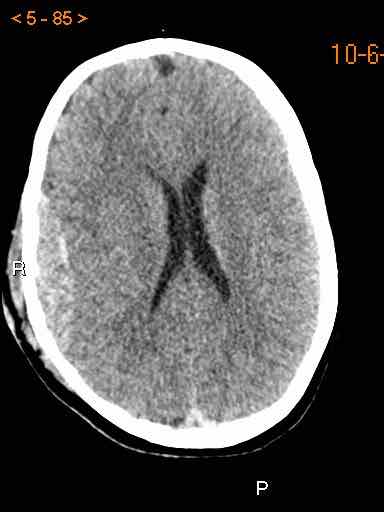

Tụ máu dưới màng cứng đồng tỷ trọng

Khi tụ máu dưới màng cứng tiến triển theo thời gian, tỷ trọng của khối tụ máu sẽ giảm dần và có thể tương đương với tỷ trọng của nhu mô não, khiến việc phát hiện tổn thương trở nên khó khăn.

Đây là trường hợp tụ máu dưới màng cứng đồng tỷ trọng rất khó phát hiện (các mũi tên).

Lưu ý rằng ở mức cắt cao hơn có tụ máu dưới màng cứng hai bên.